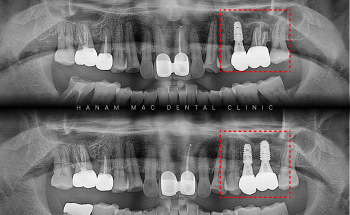

[임플란트 치료 기록] 하악 전치부 임플란트 및 상악동 거상술 동반 어금니 식립 69세 환자분께서 "아래 앞니 임플란트하고 싶어요"라는 C.C...